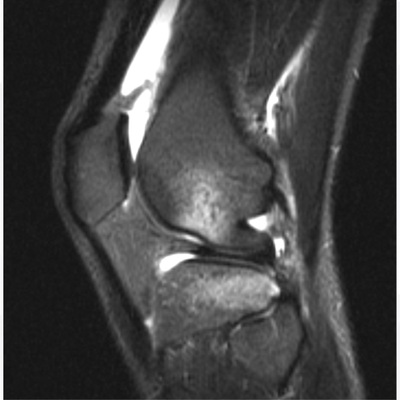

Click on an image below to view more info.